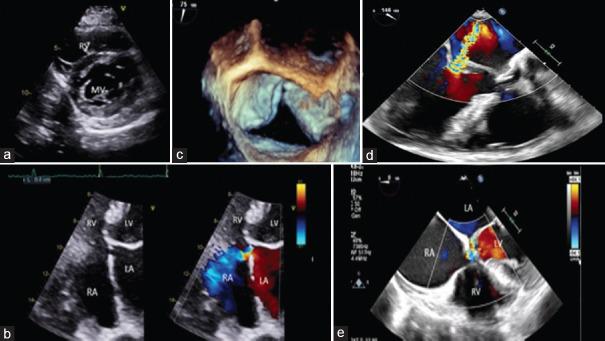

This article provides comprehensive insights into the evaluation of simple congenital heart diseases (CHDs) in adults, emphasizing the pivotal role of echocardiography. By focusing on conditions such as congenital aortic stenosis, aortic coarctation, patent ductus arteriosus, atrial septal defects (ASDs), and ventricular septal defects (VSDs), the review underscores echocardiography's intricate contributions to precise clinical decision-making. Echocardiography serves as the primary imaging modality, offering high-resolution visualization of anatomical anomalies and quantification of hemodynamic parameters. It enables tailored therapeutic strategies through its capacity to discern the dimensions, spatial orientation, and dynamic shunt dynamics of defects such as ASDs and VSDs. Moreover, echocardiography's advanced techniques, such as tissue Doppler imaging and speckle tracking, provide detailed insights into atrial mechanics, diastolic function, and ventricular filling kinetics. Integration of echocardiographic findings into clinical practice empowers clinicians to create personalized interventions based on quantified ventricular function, which spans systolic and diastolic aspects. This approach facilitates risk stratification and therapeutic planning, particularly pertinent in heart failure management within the CHD patient population. In summary, echocardiography transcends its role as an imaging tool, emerging as a precision-guided instrument adept at navigating the complexities of simple CHD in adults. Its ability to expedite diagnosis, quantify hemodynamic impacts, and unravel multifaceted functional dynamics culminates in a comprehensive depiction of these conditions. The fusion of these insights with clinical expertise empowers clinicians to navigate the intricate pathways of CHD, crafting tailored therapeutic strategies characterized by precision and efficacy.